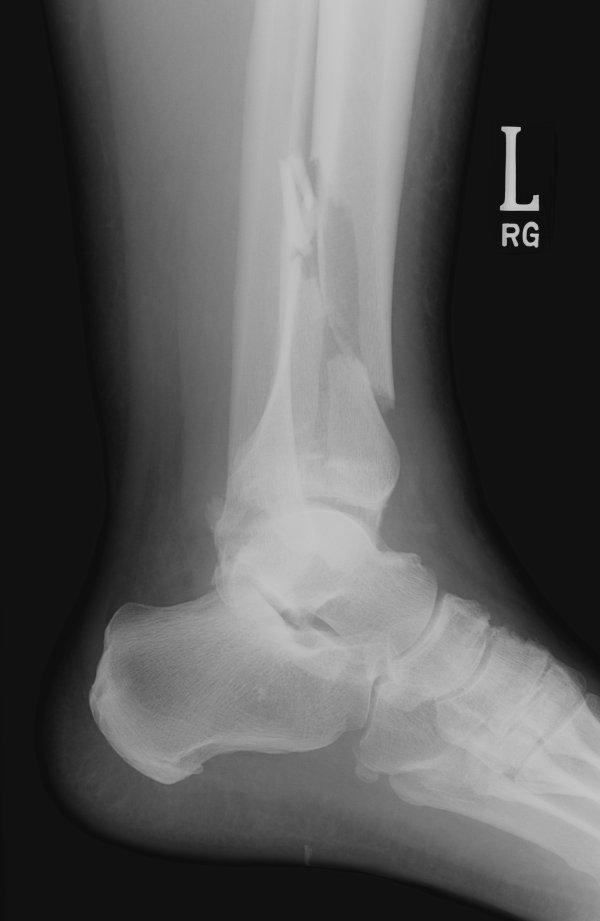

Return to Pilon Fracture